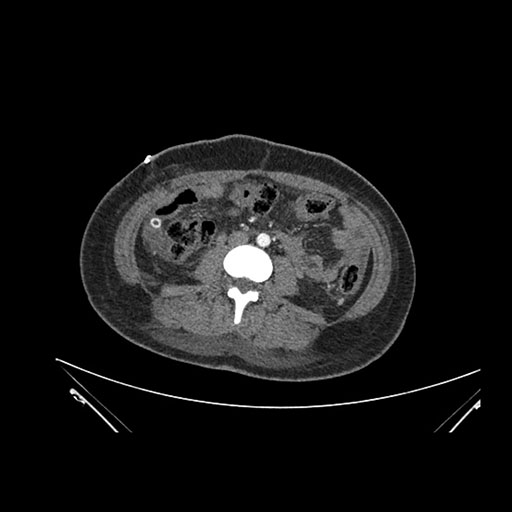

Axial Venous